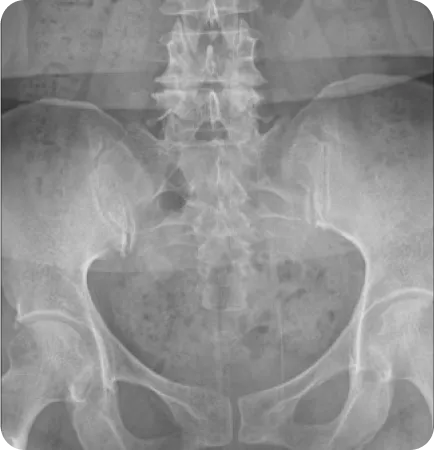

성인의 80%~90%에서 골반 부정렬이 발견되었으며,

그 중 3분의 1은 무증상, 3분의 2는 요통, 골반통 등의 증상을 호소한다.

Wolf Schamberger - The Malalignment Syndrome 中